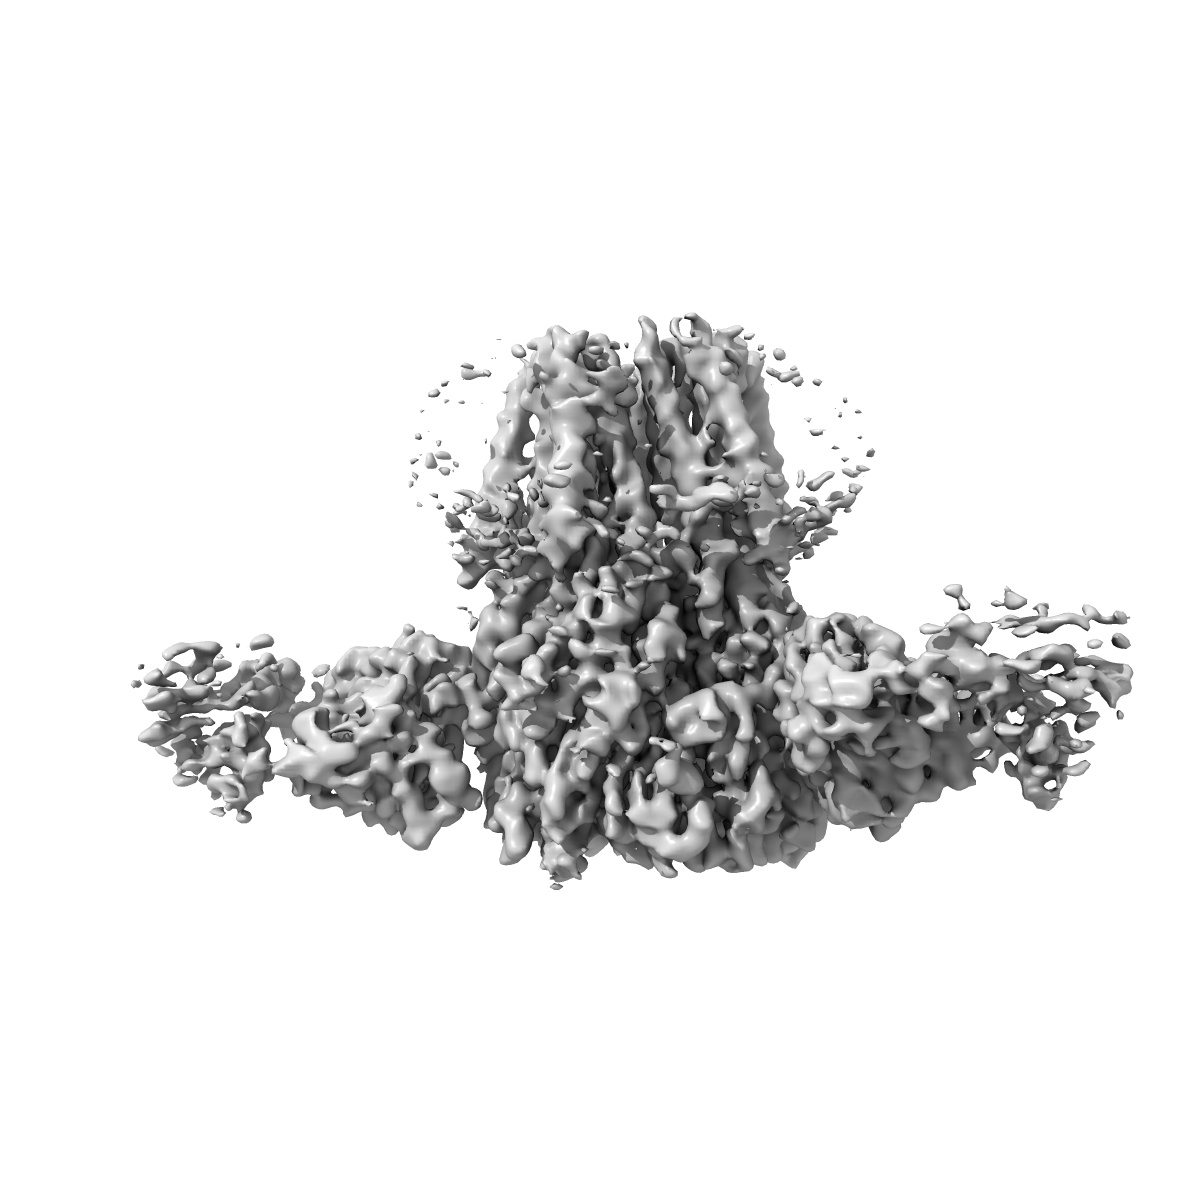

Native GABA-A receptor from the mouse brain, alpha1-beta2-gamma2 subtype, in complex with didesethylflurazepam and endogenous GABA

Sample: Native GABAA Receptor isolated from mouse brain containing two alpha1 subunits, in complex with 8E3-Fab, didesethylflurazepam, and endogenous GABA

Cryo-EM structures reveal native GABA A receptor assemblies and pharmacology.

Sun C, Zhu H, Clark S, Gouaux E

(2023) Nature , 622 , 195 - 201